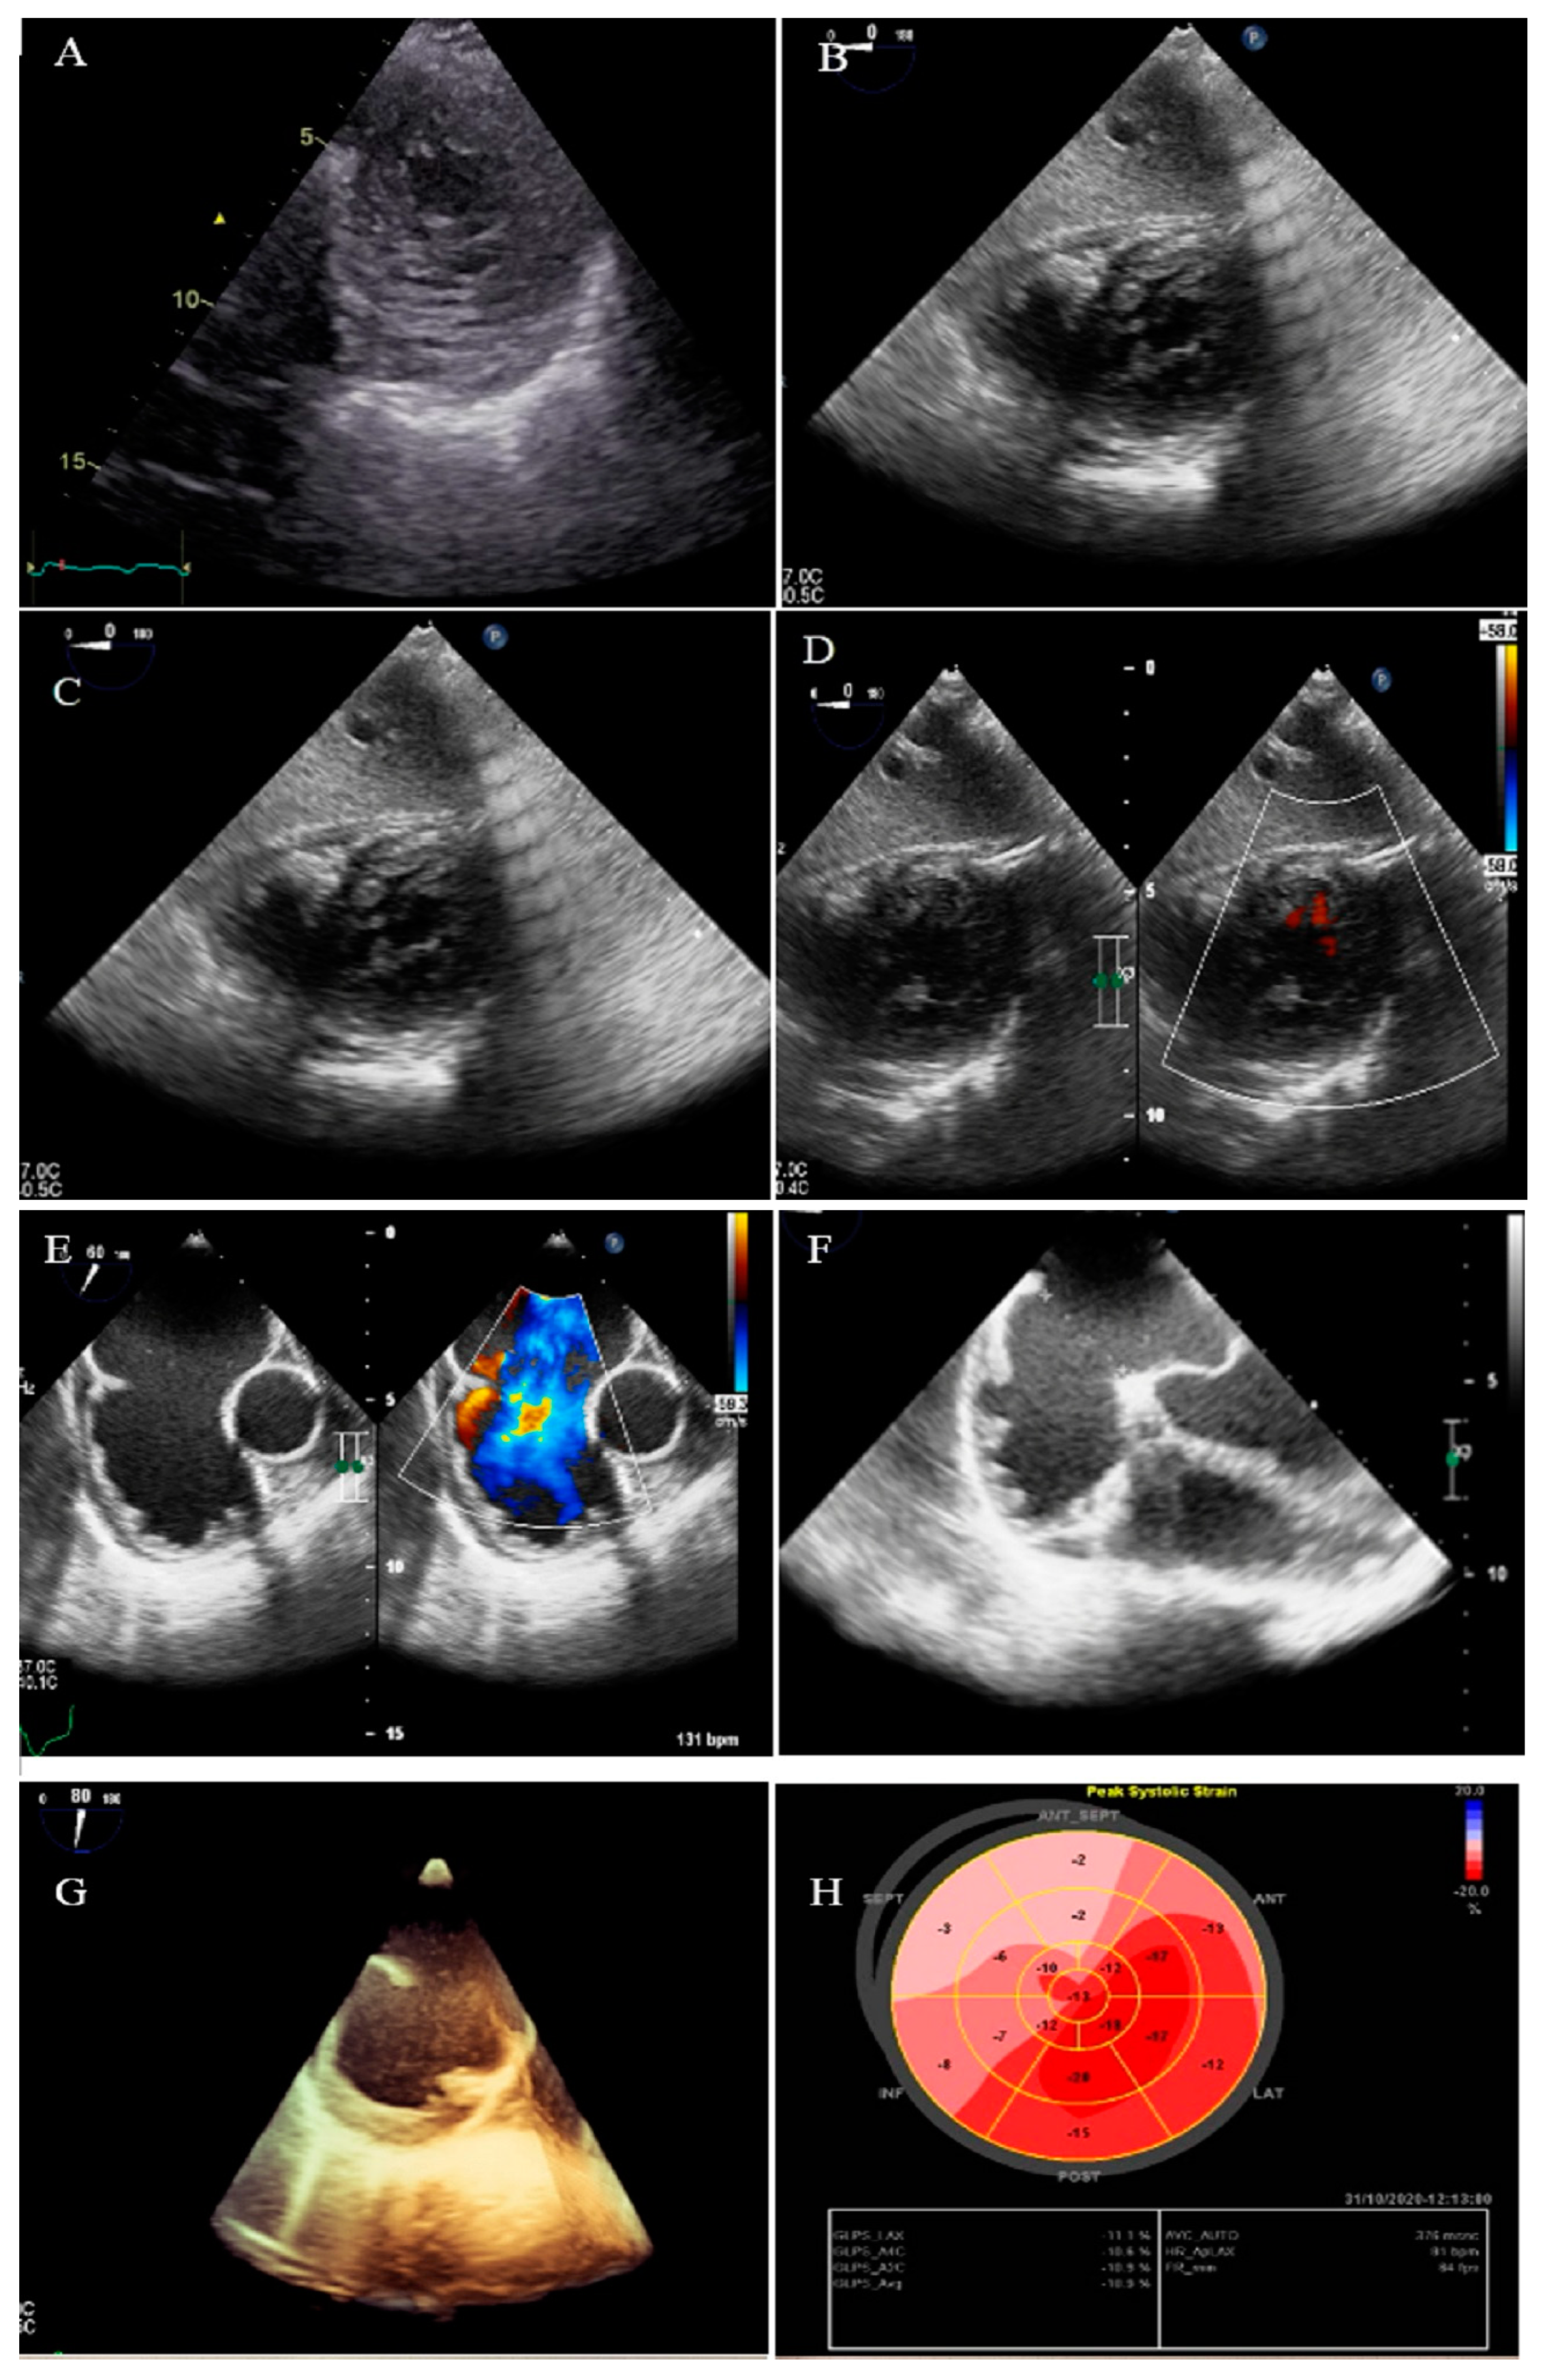

2.4. Case #4. Biventricular Non-Compaction (BVNC) with Ostium Primum Atrial Septal Defect (ASD) Plus Complete Heart Block

| 4 | F | 34 | Dyspnea, two hours after admission, she experienced sudden cardiac death, resuscitated successfully with no sequela | − | BVNC, LVEF = 45% | BAV, ostium primum atrial septal defect plus complete heart block | − | − | Single-chamber implantable cardioverter-defibrillator | No high ventricular rate for 4 months |